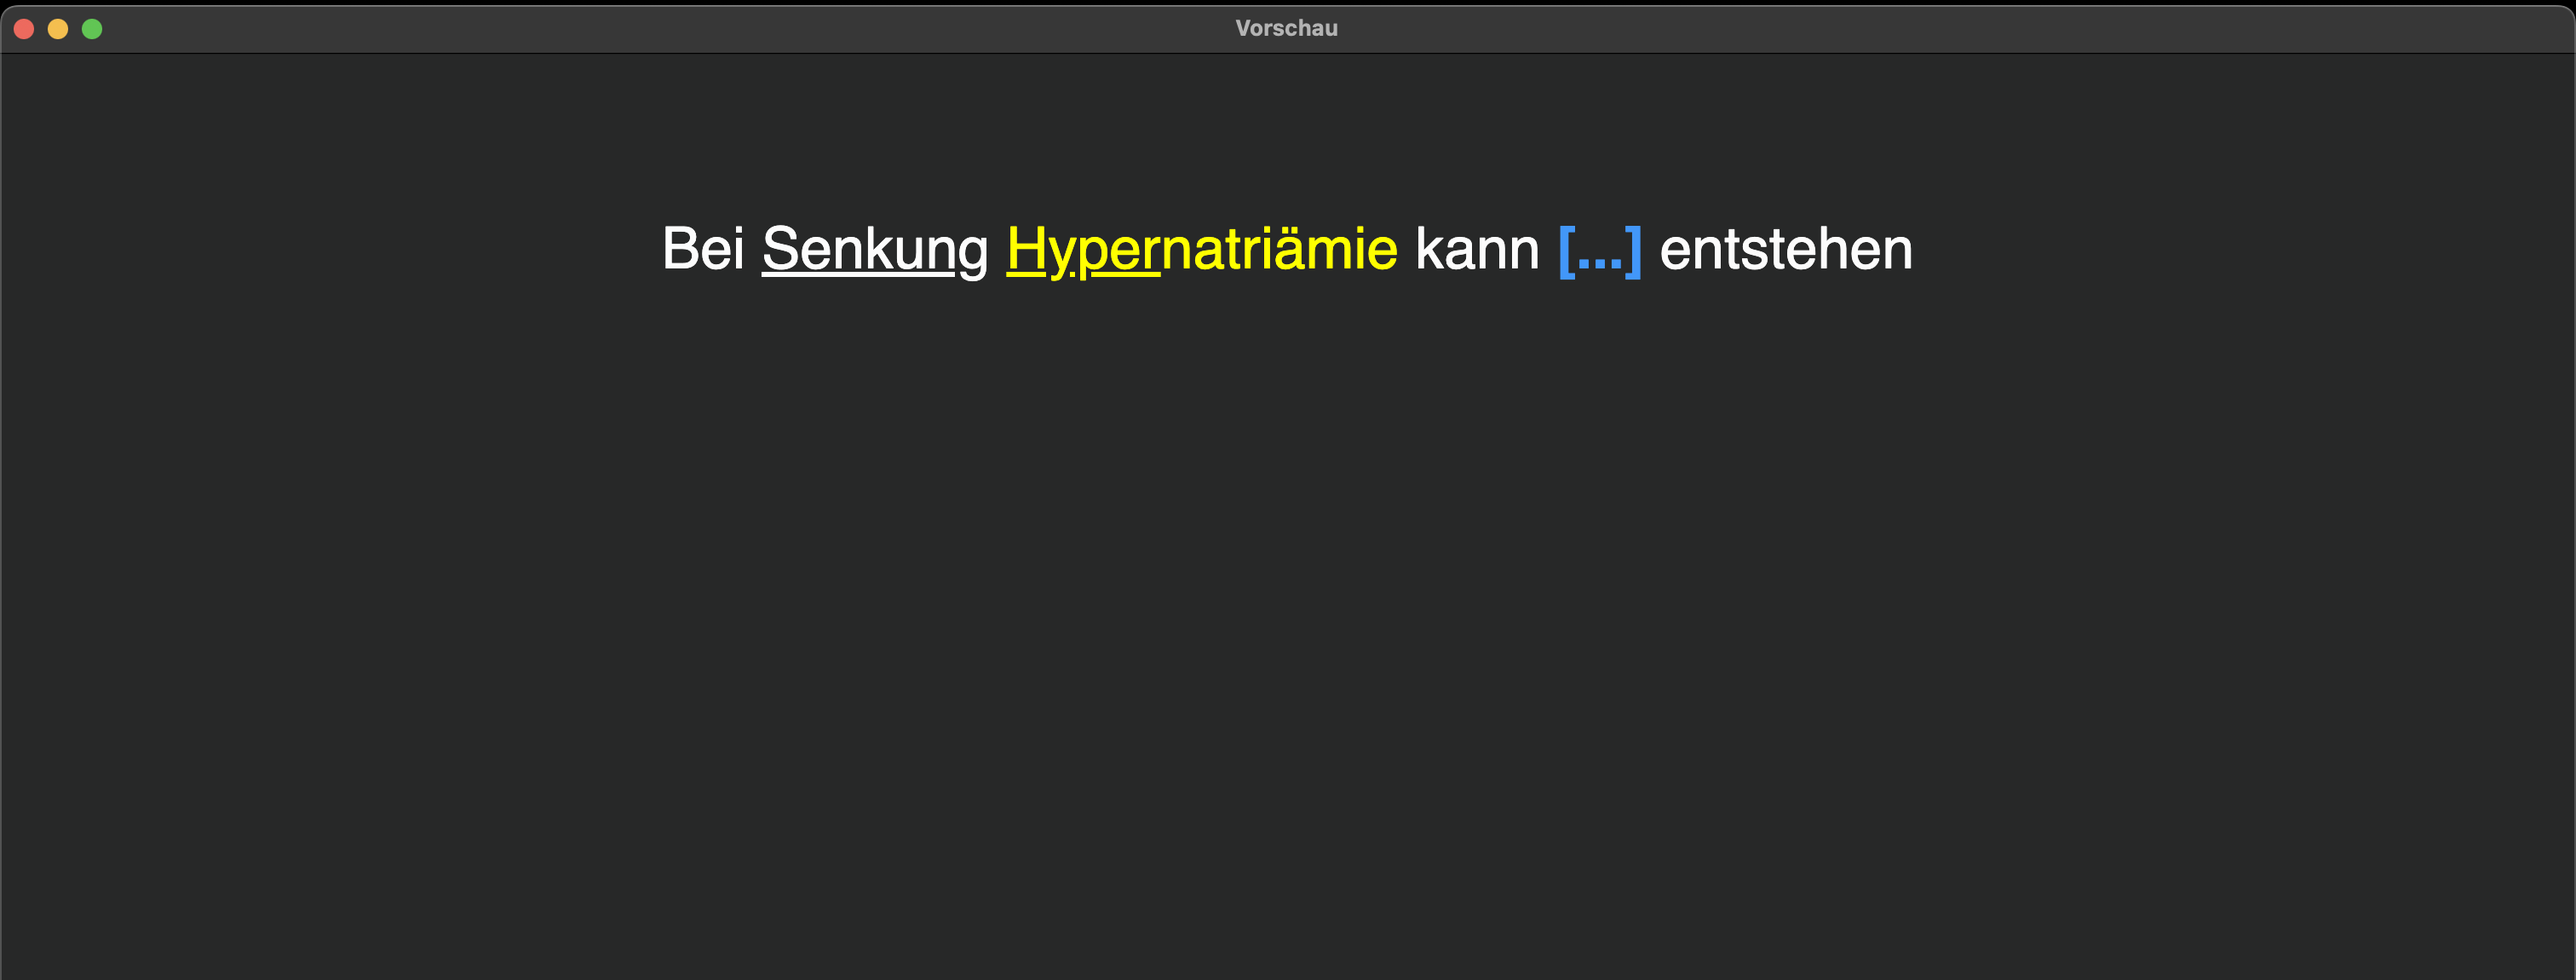

3 Reduce

Wenn auf einer Karte absolut nur die relevanten Informationen sind, spart das Zeit. Und einige Sekunden pro Karte gespart ist bei vielen (tausend) Karten sehr viel gesparte Zeit 💶. Das heißt Fragentext und Antwort auf die Wörter reduzieren, welche zum Verstehen von Frage und Antwort ausreichen. Erliege nicht der Illusion, dass Informationen im Fragentext in dein Gedächtnis gelangen, nur weil du sie immer wieder siehst😉.

Außerdem Stichwörter (Auslösereize) nutzen: Verwende klare, einheitliche Stichwörter in deinen Anki-Fragen, damit dein Gehirn sofort weiß, was gefragt ist. Sie aktivieren im Gehirn zuverlässig und schnell das passende Wissensfeld. Wenn du sie einheitlich nutzt, vermeidest du Verwirrung und beschleunigst das Erinnern. Beispiele:

Wenn dadurch mehrere Items abgefragt werden, sollte die Anzahl kenntlich gemacht werden, um deinem Gehirn eine komfortable mentale Antwort-Fahrbahn zu ermöglichen:

Weiteres Beispiel:

Weiteres Beispiel: